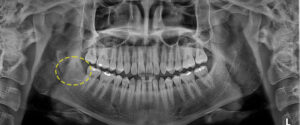

두 번째 환자분을 소개해 드릴께요.

위 환자분은 상악 좌측을 제외한

모든 곳에 사랑니를 가지고 계셨는데요.

파노라마 사진을 보시면 하악 좌측 사랑니는

치아가 수평 매복 되어 있고,

하악 우측 사랑니는 신경관을 물고

위치해 있는 것처럼 보였어요.

첫 번째 환자분에 비해 난이도가 더 높아보이죠?

CT 촬영 결과 다행히 신경관과 가까이

위치해있긴 하지만, 신경관을 물고 있는

상태는 아니라 발치가 가능했으며

신경관을 건드리지 않도록

주의가 필요했어요.

발치 후 파노라마 사진을 보시면

깔끔하게 발치된 모습을 보실 수 있어요.👀